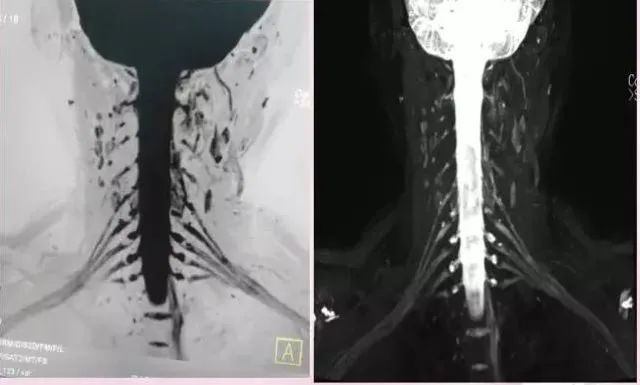

二、查脊柱病变

脊柱椎间盘、椎间关节、韧带的退行性变,椎管狭窄、椎管内肿瘤、血管畸形,椎间盘突出,骨结节,脊椎滑脱等病变都能很好的定性定位。

常见症状:颈部不适,上肢麻木,胸背部压痛,腰痛,下肢麻木,尿潴留。